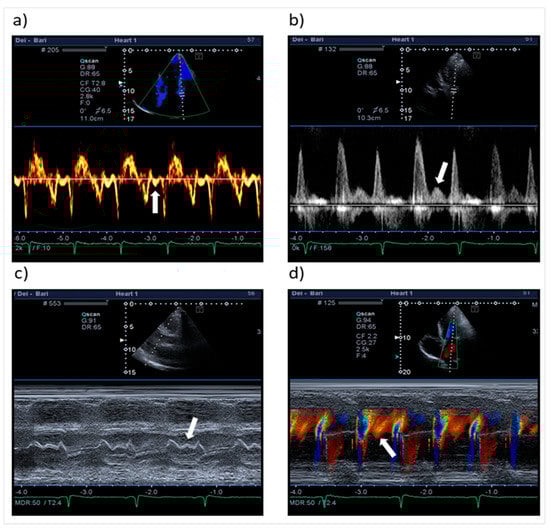

| Mid-diastolic transmitral flow velocity (L wave) | Distinct forward flow velocity after E wave with peak velocity ≥ 20 cm/s | Apical four-chamber view, sample volume at the tips of mitral leaflets with PW Doppler |

| Mid-diastolic mitral valve motion (L motion) | Mid-diastolic opening and closing motion of the mitral valve | Parasternal long-axis view M-mode along the line-cutting mitral valve |

| Mid-diastolic mitral annular velocity (L’ wave) | Distinct basilar–apical tissue velocity after E’ wave present in all cardiac cycles * | Apical four-chamber view, sample volume at septal and lateral mitral annular corners (TDI and PW Doppler) |